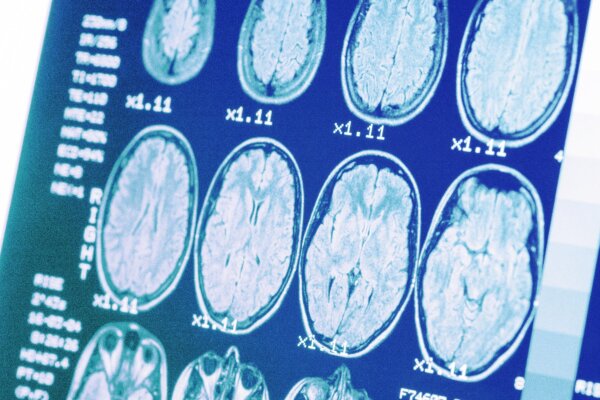

Stroke: A Condition That Occurs Every 40 Seconds With Lasting Effects—Watch Out for Signs

Stroke symptoms usually come on suddenly and are most severe at the start. In some cases, they may come and go or worsen gradually—and sometimes a person may not even realize they have had a stroke. Here are warning signs to watch for.